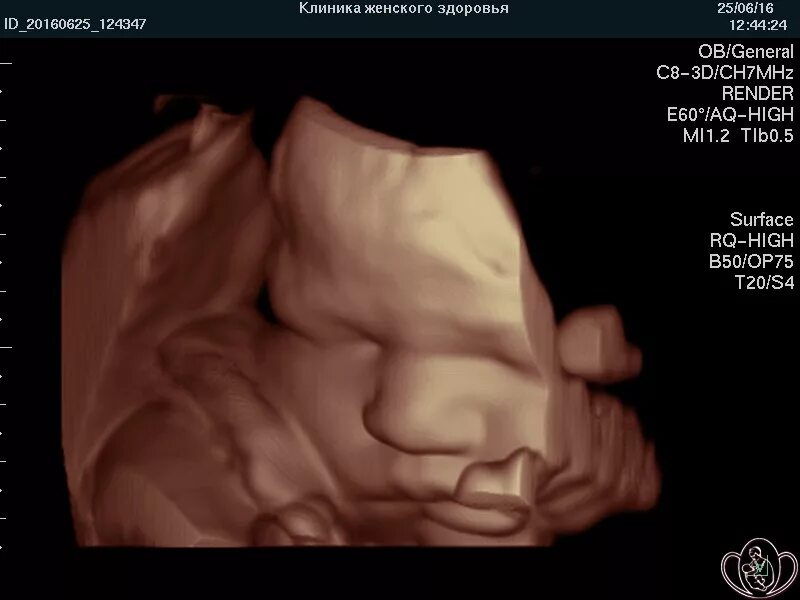

Скрининг 30 недель